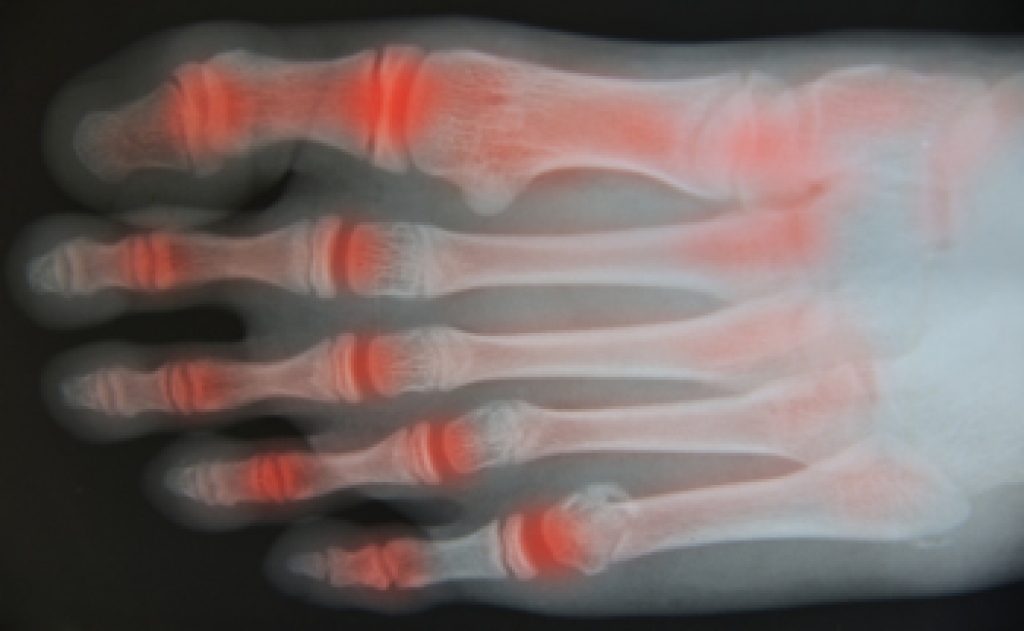

Foot and ankle injuries are a common occurrence when it comes to athletes of any sport. While many athletes dismiss the initial aches and pains, the truth is that ignoring potential foot and ankle injuries can lead to serious problems. As athletes continue to place pressure and strain the area further, a mild injury can turn into something as serious as a rupture and may lead to a permanent disability. There are many factors that contribute to sports related foot and ankle injuries, which include failure to warm up properly, not providing support or wearing bad footwear. Common injuries and conditions athletes face, including:

Sports related injuries are commonly treated using the RICE method. This includes rest, applying ice to the injured area, compression and elevating the ankle. More serious sprains and injuries may require surgery, which could include arthroscopic and reconstructive surgery. Rehabilitation and therapy may also be required in order to get any recovering athlete to become fully functional again. Any unusual aches and pains an athlete sustains must be evaluated by a licensed, reputable medical professional.